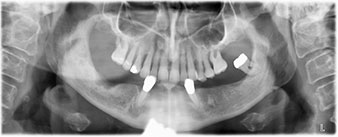

A three-dimensional cone beam computed tomography scan (CBCT, Planmeca) was performed to aid planning and minimize risks. This revealed that the quality and quantity of the available bone were sufficient for the surgery and immediate restoration using the Fast & Fixed method. Following the protocol for this concept, the implants are inserted at 35, 32, 42 and 45. Angling the distal implants by up to 45° shifts the emergence profile to posterior and generates a larger support polygon (Fig. 3).

Fig. 3